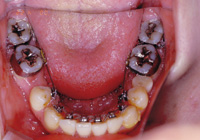

2.ブラケット:

歯に装置を接着して、ワイヤーを用いて歯並びを治します。

<裏側矯正装置>